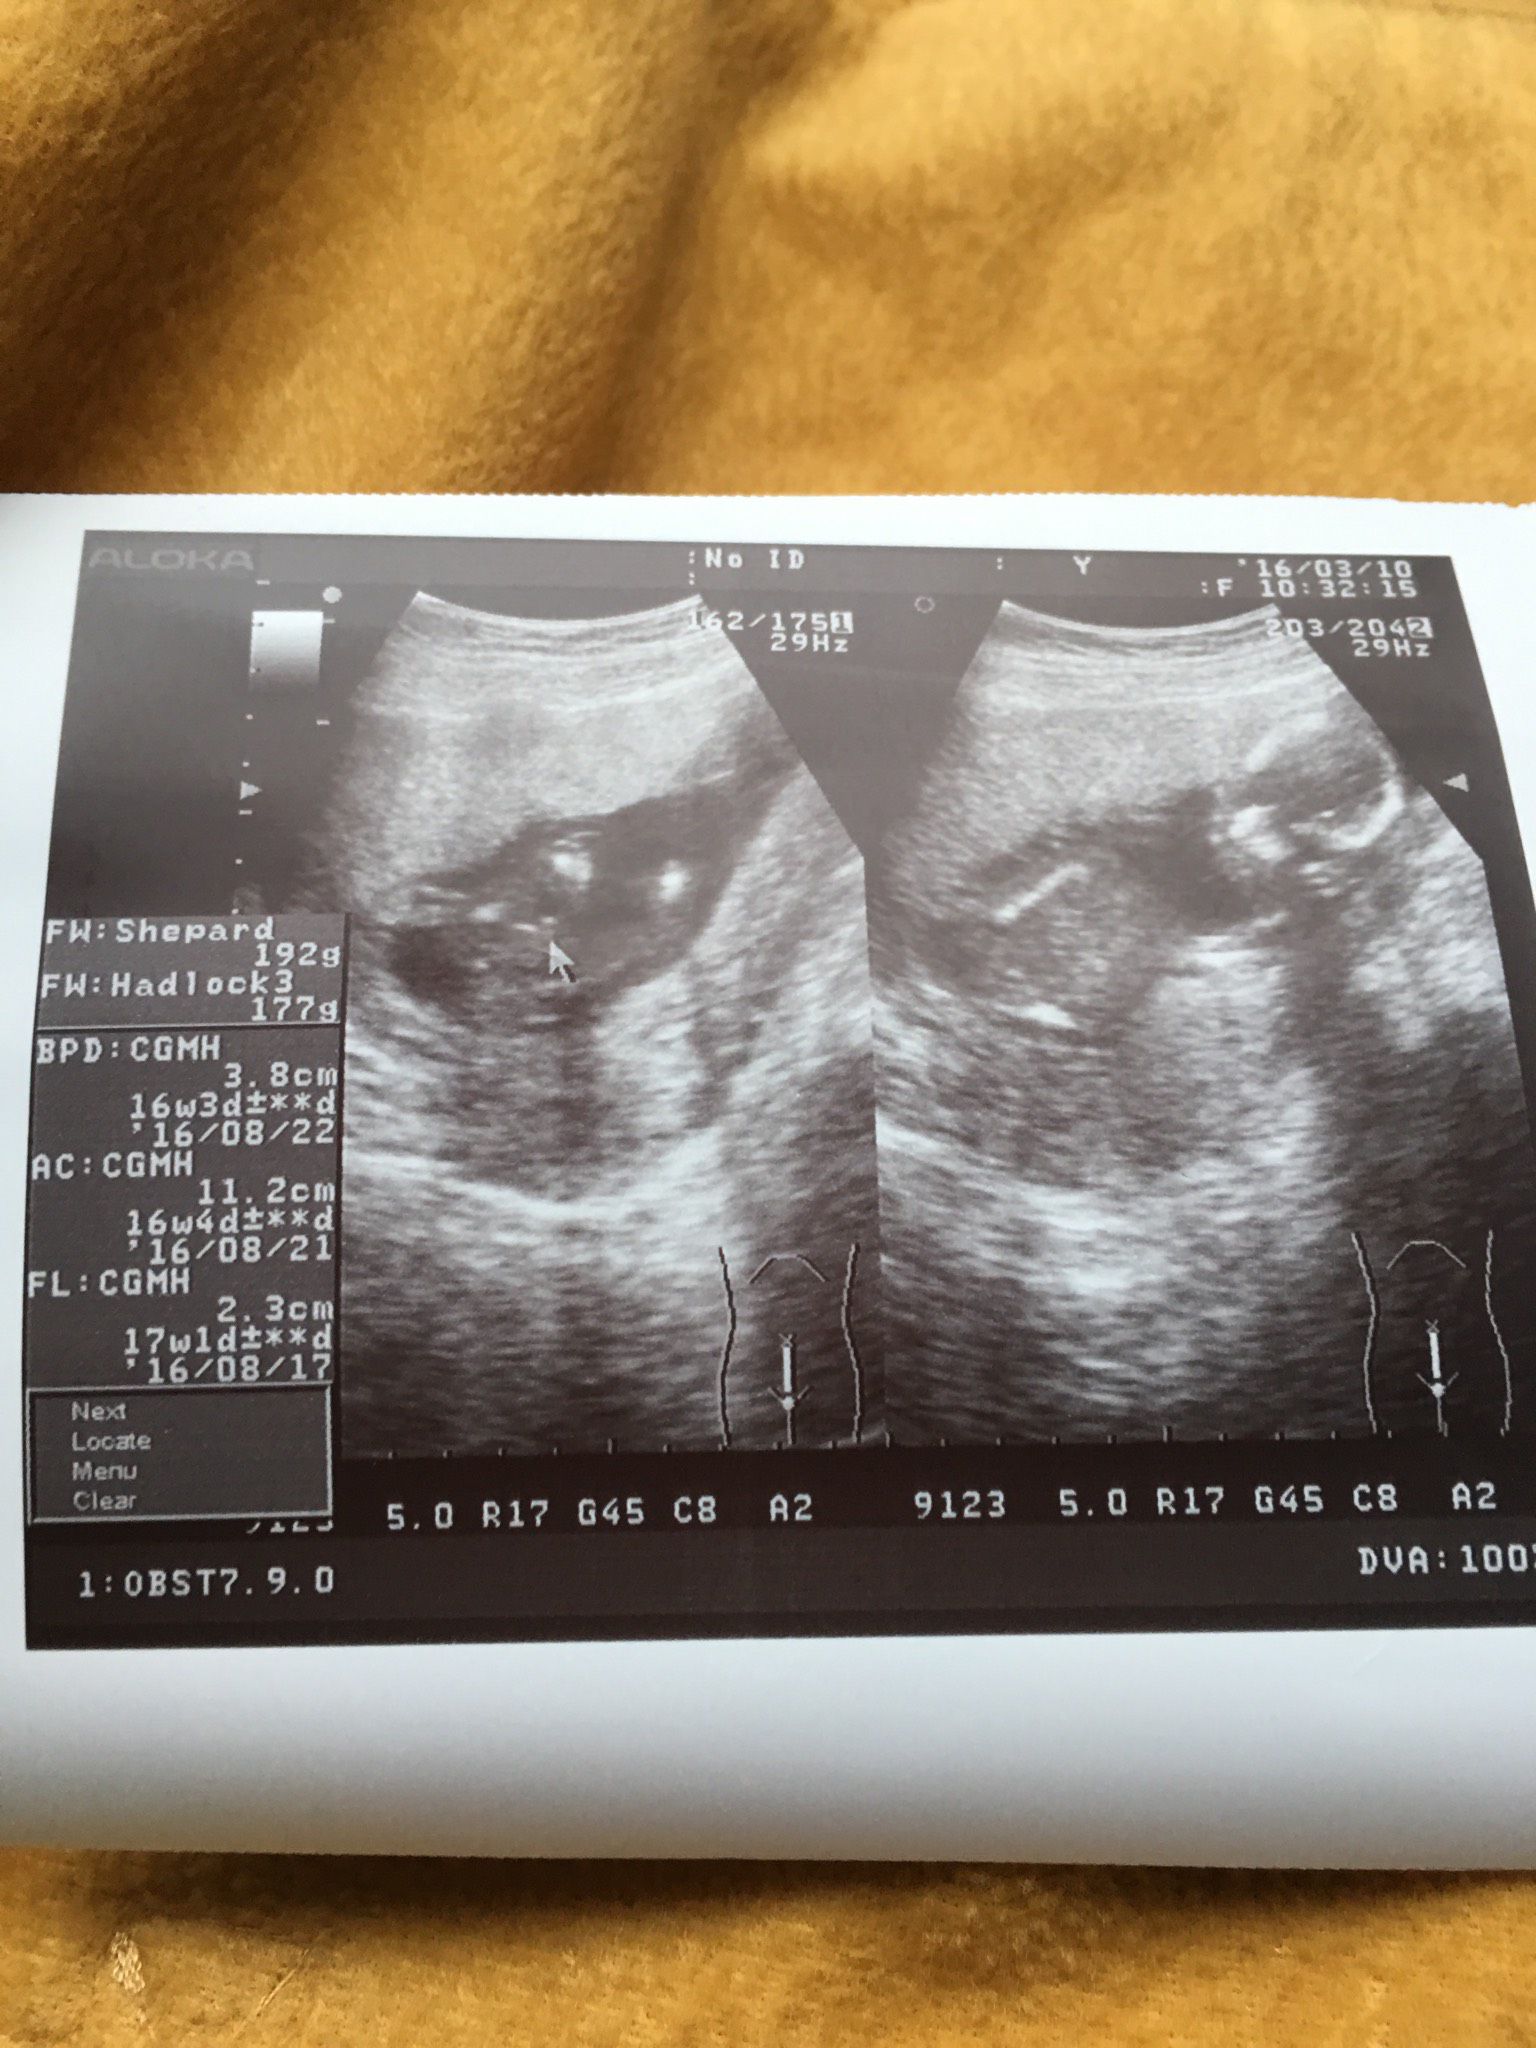

16+4 請問媽咪們看得出來是男寶寶還是女寶寶嗎?

醫生好像蠻肯定說是男寶寶,但我看不出小雞雞在哪,真的是男寶寶嗎?